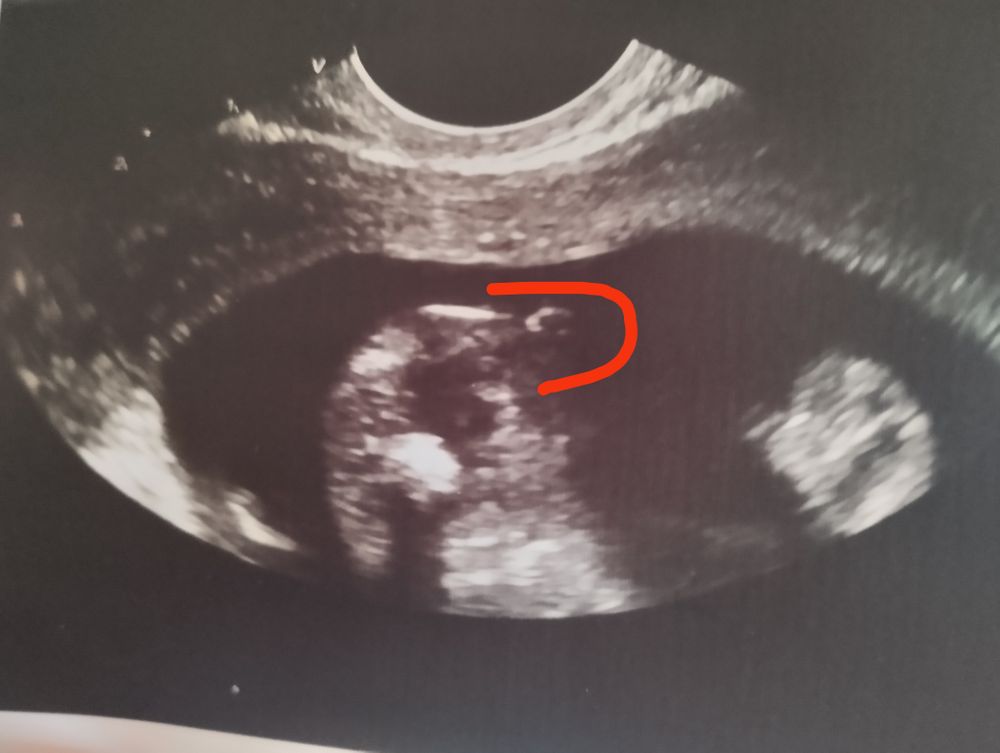

Похоже на машонку, но у меня в прошлую беременность в 17 недель прям отчетливый писюн было видно, без сомнений. А сейчас вот у меня проблема, сегодня была на узи срок 16 недель, узистка предположила девочку, так как есть бугорок, фото сделано снизу, приложу сюда, вдруг кто разбирается. Два сына есть, и все подругому было Изображение

Ны пЫську похоже девичью... Но может ошибаюсь

Мне кажется парень

Елизавета, это попа и нога

Елизавета, вид снизу

Елизавета, да это ножка и попа,вид снизу

Екатерина, все рассмотрела)) Мне кажется это машонка и это мальчик)

Елизавета, предположили мальчика,да и быстро всё так показал)но мне до сих пор не верится,я была настроена почему то на девочку)